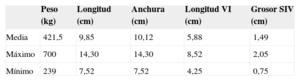

RESULTADOSInvestigación básicaEstudio anatómicoInicialmente se tomaron las medidas básicas de los corazones mostrados en la tabla 1. Los resultados de disección cadavérica de corazones humanos mostraron que los 41 corazones tenían al menos 2 FT. La media de los hallados fue 3,7. Los dividimos según sus características visuales de grosor en los más gruesos, musculares (M), y más delgados, tendinosos (T), que son de menores longitud y grosor (tabla 2).

Resumen de las características generales de los corazones estudiados por disección cadavérica

| Peso (kg) | Longitud (cm) | Anchura (cm) | Longitud VI (cm) | Grosor SIV (cm) | |

|---|---|---|---|---|---|

| Media | 421,5 | 9,85 | 10,12 | 5,88 | 1,49 |

| Máximo | 700 | 14,30 | 14,30 | 8,52 | 2,05 |

| Mínimo | 239 | 7,52 | 7,52 | 4,25 | 0,75 |

SIV: septo interventricular; VI: ventrículo izquierdo.